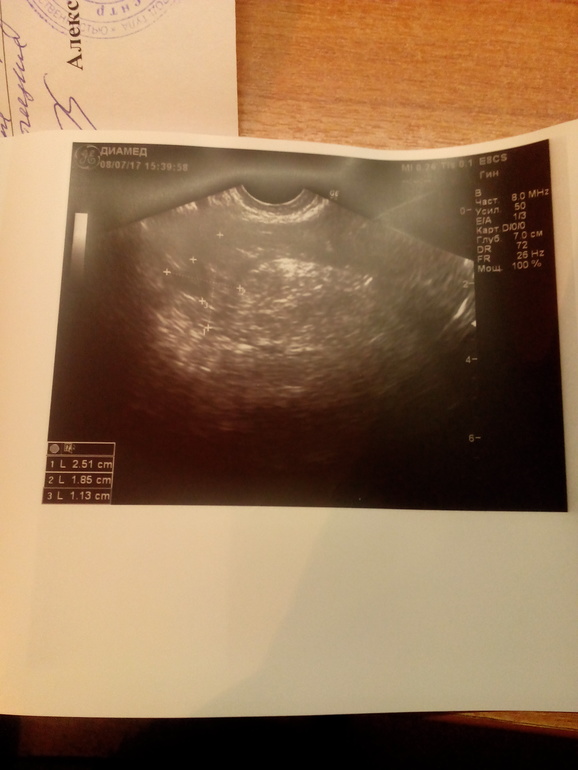

Елена

УЗИ она мне вчера сказала, что по размеру пя оно соответствует 3-4 АКУШЕРСКИМ неделям!!! Она это подчеркнула, что не эмбриональным, а акушерским

В 3 акушерских недели, ПЯ не видно вообще ( ибо это аж за неделю до М)

А узи что показало? Вообще, трудно поверить, что врач сослалась на нормы хгч на таком сроке...тут только узи имеет смысл